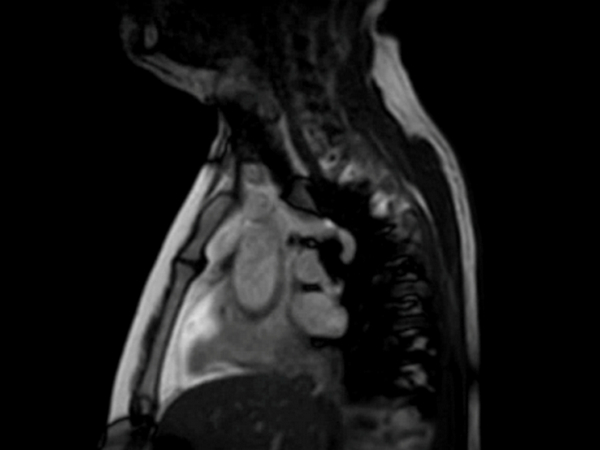

Sagittal bFFE cine